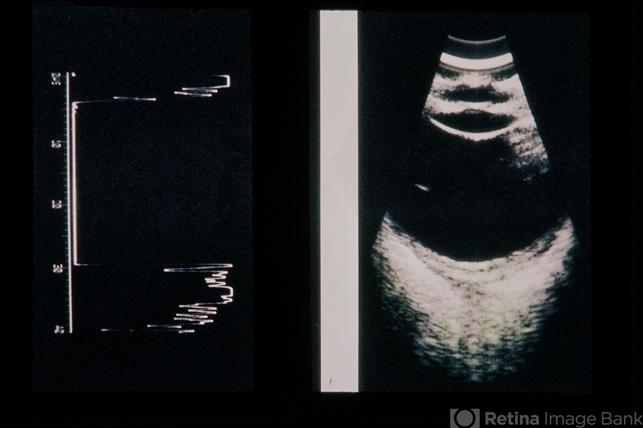

- scleritis, ocular ischemic syndrome

- 41-year-old female, scleritis / OIS.